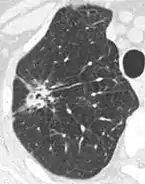

- Margin morphology: a spiculated margin is a risk factor for cancer.[8] Benign causes tend to have a well defined border, whereas lobulated lesions or those with an irregular margin extending into the neighbouring tissue tend to be malignant.[10] In particular, spiculations are highly predictive of malignancy with a positive predictive value up to 90%.[9] Also, a "notch sign", which is an abrupt indentation of the nodule, increases the risk of cancer, but may also be found in granulomatous diseases.[9]

Round well-delineated solid lung nodule with smooth border.[9]

Lobulated nodule.[9]

Spiculated lung nodule.[9]

A "notch sign".[9]

A triangular perifissural node can be diagnosed as a benign lymph node.[9]